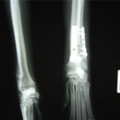

症例3:キルシュナーワイヤーのピンニングによる整復

ペルシャ猫 11ヶ月齢 雄

他院にて左大腿骨遠位の成長板骨折(salter-harrisⅠ型)が認められており、治療相談を目的として来院。当院にて、キルシュナーワイヤーを用いたピンニングにより骨折部位の整復を行いました。術後の経過は良好で、現在も経過観察中です。

術前レントゲン

術後レントゲン